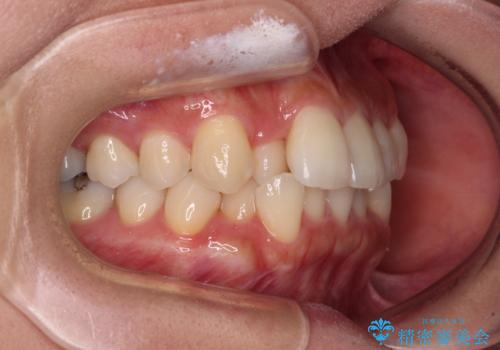

- 前歯のクロスバイトと口元の膨らんだ横顔の印象を気にして来院された患者様です。

ご本人の気にされている口元は、分析数値からするとそれほど突出しているものではありませんでした。

しかしながら。そのまま叢生を解消すると横顔が突出した印象になる可能性が高かったため、上下左右の小臼歯4本を抜歯して、ワイヤー装置にて矯正治療を行うこととしました。

上下左右の第一小臼歯4本を抜歯して治療を行うことがセオリーでしたが、左下は第二小臼歯が銀歯であったため、イレギュラーではありますが、そちらを抜歯しました。

その影響で治療期間は長くなりましたが、処置していない歯を保存することができました。